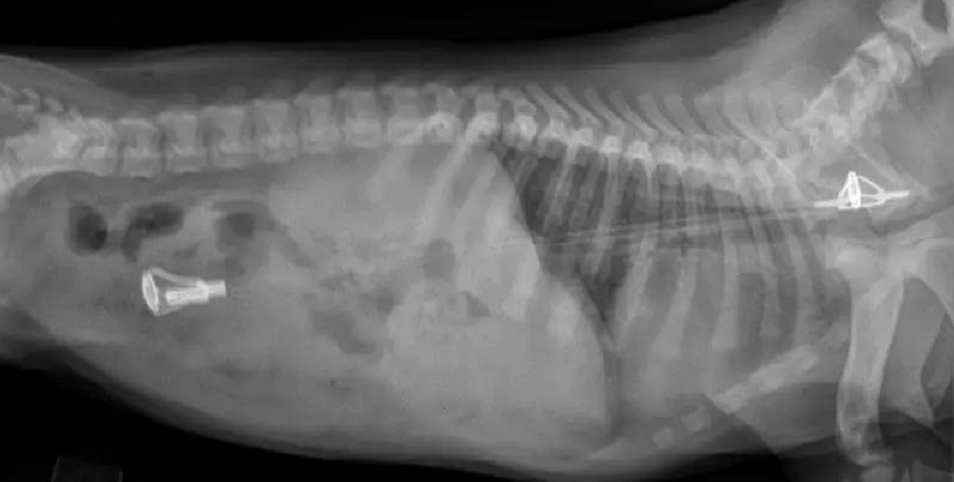

医生熟练地来了一套触诊和X光

看到片子的那一刻,

医生也迷惑了:

这密密麻麻的颗粒,和敦实的触感

只能初步判断是一条毛巾。